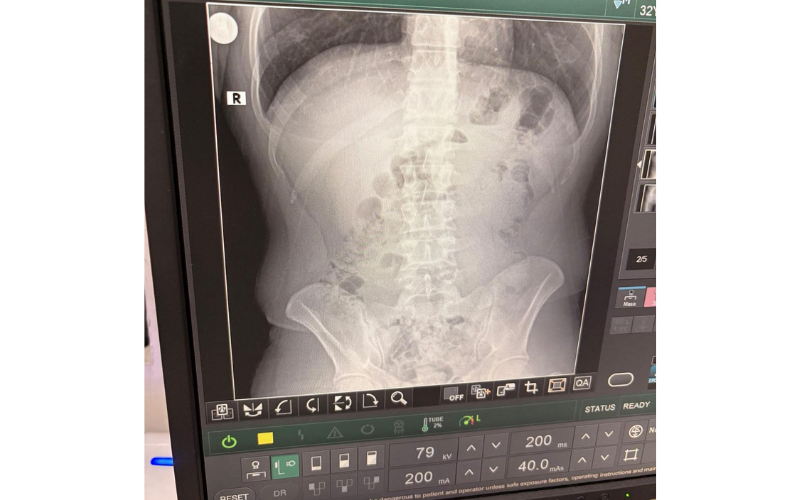

Ancak, ele geçirilen maddelerin paketlenme şeklinden şüphelenen ekipler, şahısları Uşak Eğitim ve Araştırma Hastanesi"ne sevk etti. Burada çekilen röntgen filmleri sonucunda, şüphelilerin mide ve bağırsaklarında çok sayıda kapsül bulunduğu ortaya çıktı.

Yapılan tıbbi müdahaleler sonucunda, toplam 140 kapsül halinde 1 kilo 516 gram yasaklı madde vücutlarından çıkarıldı